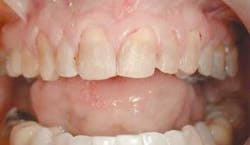

A patient came to my office (fig. 1) with some legitimate esthetic concerns. She had feldspathic porcelain veneers done 16 years ago in an effort to cover dark tetracycline staining. The patient reported being very satisfied with the outcome at the time. However, as time passed, the smile she once felt so good about began to make her feel self-conscious again.

From this information, we are able to ascertain many things. First, after ruling out any periodontal disease and noting a comfortable and asymptomatic TMJ, we can turn our attention to the esthetic concerns. As you can see in figure 2, there are many things that can be improved. Let's go through this very methodically, using principles taught by the experts in the field, and see what we can improve.